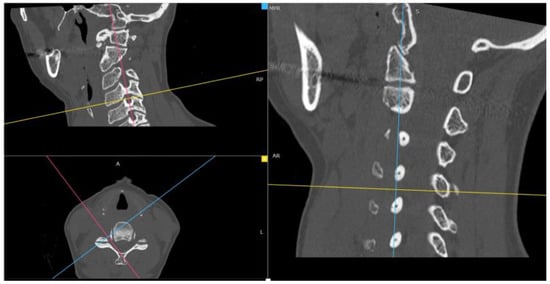

Through the use of MIP and MPR cervical bone-window CT scans, the correct site for measurements at each cervical segment (surgical or above or below) was selected matching the midline point on the anterior surface of the vertebral body on coronal view with the intervertebral foramen plane on axial view, and then adjusted with a plane parallel to the inferior endplate of the level above on the sagittal view. (Figure 1). The antero-posterior (A-P) and cranio-caudal (C-C) diameters of each foramen (surgical and adjacent levels, right and left) were manually measured (Figure 2a). The measurement of the C-C diameter was considered similar to the height of the foramen, and in sagittal reconstruction it was the distance between the midpoint of the upper and lower corresponding pedicles; the measurement of the A-P diameter was considered similar to the width of the foramen, and in sagittal reconstruction it was the distance between the anterior and the posterior border of the inferior intervertebral notch. For the intervertebral disc measurement, the disc height was measured in the anterior, middle, and posterior third on sagittal CT scans. The measure of the intervertebral disc space was considered from the corresponding point (anterior, middle, and posterior) of the inferior endplate of the upper vertebral body to the superior endplate of the lower vertebral body (Figure 2b). CT scans were performed before and within 72 h after surgery, usually the day after the procedure.

Figure 1.

Neural cervical foramen was centered using MIP and MPR CT reconstructions.